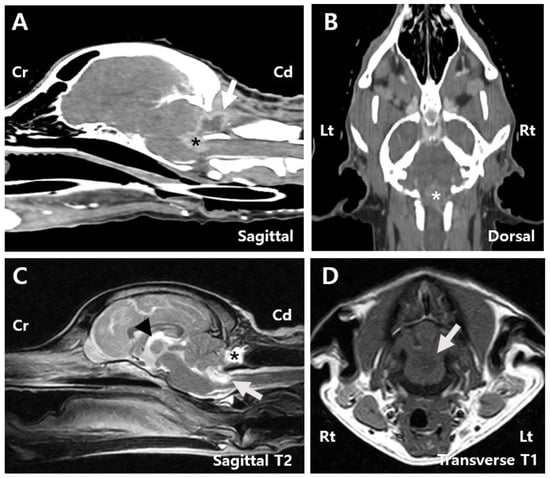

The referring clinic had previously performed magnetic resonance imaging (MRI) of the brain and spine, revealing a 1.4 cm × 1.4 cm × 2.2 cm mass at the level of the fourth ventricle and caudal part of the brainstem. The mass showed hyperintensity on T2-weighted (T2) images, hypointensity on T1-weighted (T1) images with internal areas of hypointensity on T2 images, and isointensity on T1 images. In addition, the mass showed peripheral contrast enhancement with an internal non-enhancing hypointensity (Figure 1D). A T2-star signal void was also observed, suggesting the presence of a hematoma.

The mass compressed the cerebellum and caused edematous changes in the adjacent brainstem and C2 spinal cord (Figure 1C). Mild dilation of the third ventricle and thinning of the arachnoid space across the cerebrum were also noted, indicating a high likelihood of an intra-axial tumor with associated swelling and compression. Computed tomography (CT) revealed heterogeneous contrast enhancement in the fourth ventricle and caudal brainstem, consistent in size with MRI findings (Figure 1A,B). Based on brain MRI and CT findings, the lesion was anatomically positioned to possibly originate from the fourth ventricle, suggesting a choroid plexus tumor or ependymoma. However, other possibilities, such as meningioma and glioma, could not be ruled out. Owing to the tumor’s location and the risk associated with overall increased intracranial pressure, cerebrospinal fluid paracentesis was not performed. No abnormalities or signs of metastasis were observed on chest radiography, CT, or cardiac ultrasonography.

Figure 1. Pre-surgery images. (A) Sagittal computed tomography (CT) image of the patient showing a tumor measuring 1.4 cm × 2.2 cm (asterisk). (B) Dorsal CT image showing a tumor measuring 1.4 cm × 2.2 cm (asterisk). (C) Sagittal T2-weighted magnetic resonance imaging (MRI) image displaying mild dilation of the 3rd ventricle (arrowhead), compression of the cerebellum by the mass (arrow), and edematous changes extending to the adjacent brainstem (white asterisk) and C2 spinal cord (yellow asterisk). (D) Transverse T1-weighted contrast-enhancement magnetic resonance imaging (MRI) image suggesting a hematoma within the tumor (arrow). Cd, Caudal; CE, Contrast-enhancement; Cr, Cranial; Lt, left; Rt, right.